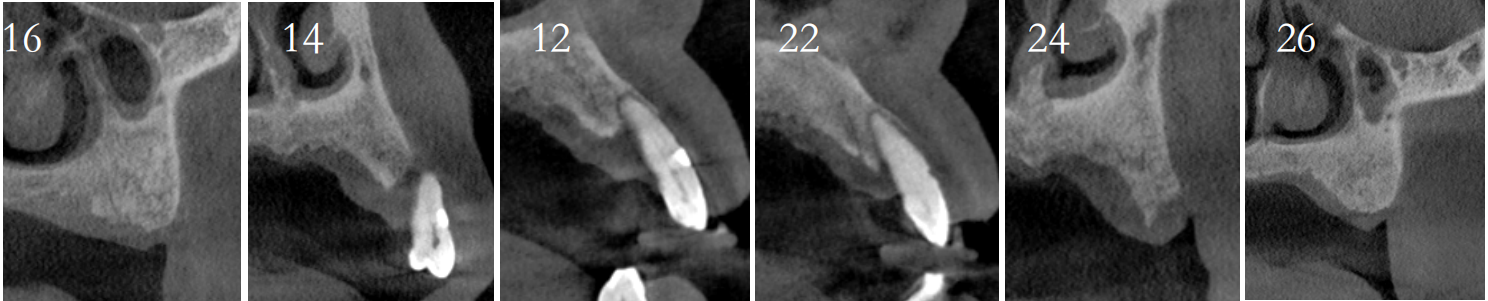

导板制作完成:

导板引导下种植手术:

上颌植入6颗中科安齿种植体